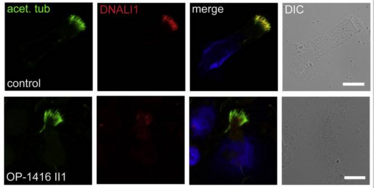

Press release: CRU326 members identified one genetic cause for male infertility

Press release: CRU326 members identified one genetic cause for male infertility

Fataler Fehler bei C11ORF70: Münstersche Uni-Mediziner identifizieren Genmutation als eine Ursache für männliche Infertilität

Fataler Fehler bei C11ORF70: Münstersche Uni-Mediziner identifizieren Genmutation als eine Ursache für männliche Infertilität